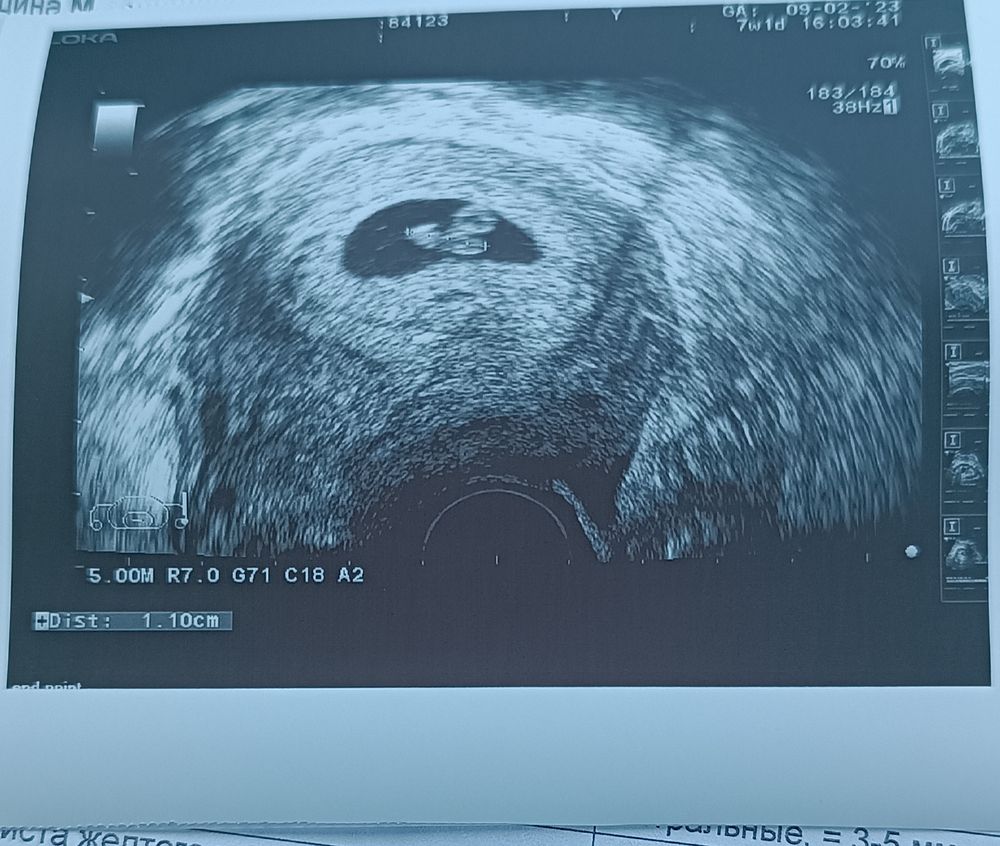

Определение пола по методу Рамзи

У меня был такой пост, посмотрите, вроде похоже, мальчик в итоге 😁

Мария, но у вас датчик сверху был, как у большинства. А у меня снизу, это получается переворачивать надо и так оценивать справа или слева?

Мария, ну то есть если бы мое фото перевернуть.

Кгт непонятные результаты Что это в яичнике у меня?